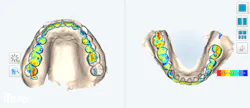

Occlusal analysis via occlusogram (figures 5 and 6) demonstrated broad, heavy contacts on the right posterior dentition, particularly between nos. 2 and 31, without corresponding support on the contralateral side. Excessive attrition was present across anterior incisal edges and posterior cusps, leading to loss of anterior guidance, compromised function, and diminished esthetics. These findings raised the critical question: if left untreated, what would this occlusion look like in five years, and how can proactive intervention restore stability and function?

Near-infrared imaging (NIRI) was employed to identify and treatment plan hard tissue concerns, including incipient interproximal lesions, microfractures, craze lines, and fluorosis. Soft tissue assessment revealed localized gingival recession, consistent with disproportionate occlusal loading and traumatic occlusal forces. These imbalances created undue tension on periodontal support structures, increasing the risk of hypersensitivity, root caries, mobility, and eventual tooth loss.